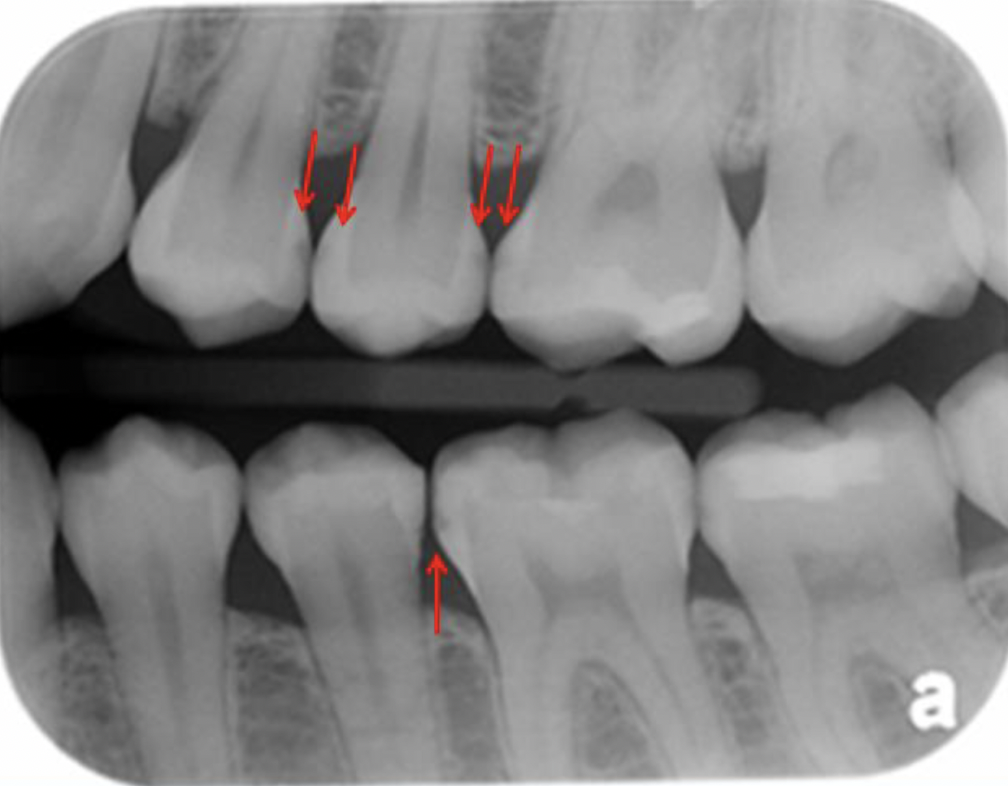

What is going on in the following radiograph?

Interproximal burnout